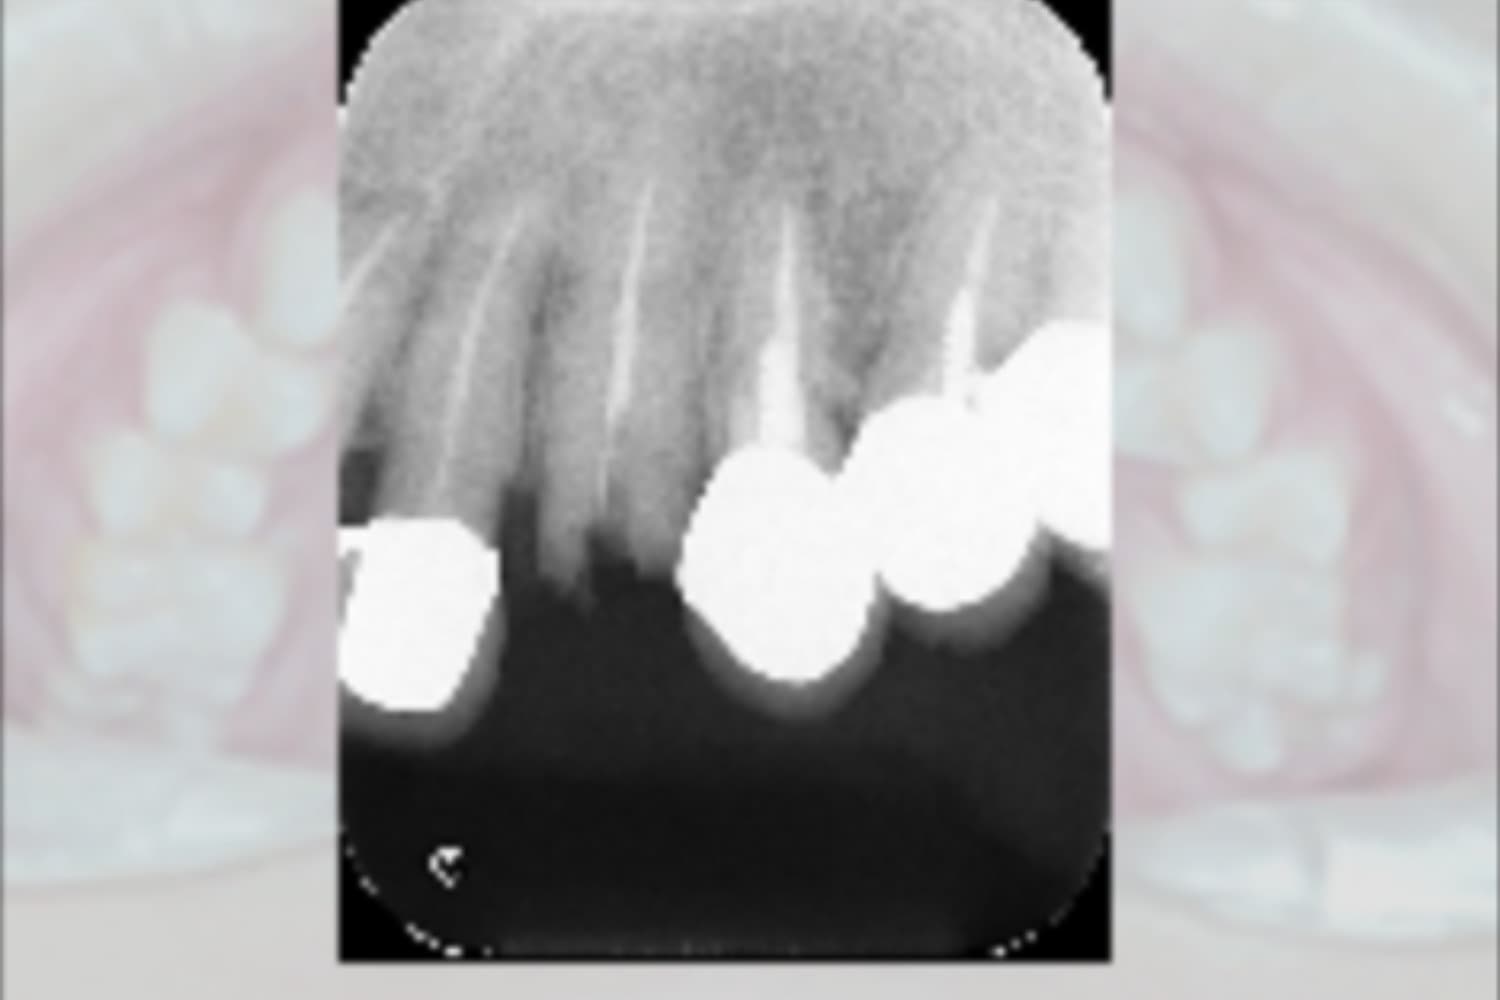

前歯のインプラント治療

Before

After

前歯4本を抜歯し、その後2本のインプラントと骨造成を行いました。上部構造は4本分です。

主訴

前歯が気になる

治療期間

12カ月

治療回数

12回

費用

1,276,000円

副作用・リスク

・重度歯周病により、感染リスクが高い ・インプラントとの結合不良が起きる可能性がある ・手術前に歯周病の十分なコントロールが必要 ・治療後も1〜2カ月ごとの定期メインテナンスが必須